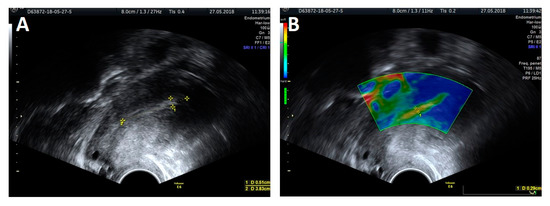

2.3. Methodology of Elastography

Figure 1. A 2D ultrasound presentation: endometrial thickness (A) and elastography: thickness measurement of the softest layer of the endometrium (B).